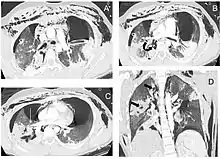

كثيرًا ما يصعب تشخيص[؟] وعلاج الإصابة الرغامية القصبية.[3] فالتشخيص المبكر يعد ضروريًا لمنع المضاعفات من الحدوث، والتي تشمل: تضيق في مجرى الهواء، وعدوى الجهاز التنفسي، وتلف في أنسجة الرئة. والتشخيص عادة ما يشمل إجراءات عدة منها تنظير القصبات، والتصوير الشعاعي، والتصوير المقطعي المحوسب الذي يظهر الشجرة الرغامية القصبية. تتفاوت العلامات والأعراض حسب موضع الإصابة ومدى شدتها، وغالبًا ما تشمل: ضيقًا في التنفس، وخلل في الصوت (حالة يكون فيها الصوت أجشًا، وضعيفًا، ومصحوبًا بأصوات مسموعة شديدة)، وسعال، وأصوات تنفس غير طبيعية. تنبيب الرغامى قد يستخدم لضمان بقاء مجرى الهواء مفتوحًا في حالات الطوارئ. كما أن التدخل الجراحي قد يعد ضروريًا في الحالات الوخيمة من الإصابة الرغامية القصبية.

التشخيص السريع والعلاج مهم لعلاج الإصابات الرغامية القصبية، وتزداد احتمالية التعرض للمضاعفات إذا لم يتم تشخيص الإصابة خلال فترة وجيزة بعد الحادث. "تنظير القصبات" هي أكثر طريقة فعالة لتشخيص وتحديد مكان ومدى خطورة الإصابة، وبالعادة تكون هي طريقة التشخيص المعتمدة. يعد التشخيص باستخدام منظار القصبات المرن والذي يسمح برؤية مباشرة، هو الطريقة الأسرع والأكثر اعتمادية في التشخيص. "تنظير القصبات" قد يكشف تهتك في مجرى الهواء، أو انسداده بسبب الدم، أو انهيار في الرغامى يحجب رؤية الشعب الهوائية.

الأشعة السينية هي أولى أدوات التصوير المستخدمة في تشخيص الإصابات الرغامية القصبية. قد لا تظهر أي علامات في الفلم إذا لم يبدي المريض أية أعراض. المؤشرات التي ينظر لها في الأشعة تشمل: تشوه في الرغامى أو خلل في جدار الرغامى نفسها. قد تُظهِر الأشعة تجمع للهواء في منطقة العنق. كما قد تُظهر الأشعة السينية علامات أو إصابات مصاحبة مثل: كسور أو انتفاخات أسفل الجلد. في حال ظهور انتفاخات أسفل الجلد وأظهرت الأشعة السينية وضعية غير طبيعية للعظم اللامي (عظمة في قاعدة اللسان) أعلى الحنجرة، قد يكون هذا مؤشر لإصابة قوية في الرغامى. كما يتم اشتباه هذه الإصابة عندما يبدو الأنبوب داخل الرغامى خارجًا عن مكانه، أو يبدو بالون الأنبوب ممتلئ بشكل يفوق العادة أو بارز في نتوءات مجرى الهواء. في حال كان التمزق على طول الرغامى، قد تنهار الرئة باتجاه القفص الصدري (عكس ما يحدث بالعادة في استرواح الصدر)؛ لأنها تفقد التصاقها بالرغامى والذي بدوره يبقيها باتجاه منتصف الصدر. عند استلقاء الشخص ووجهه باتجاه الأعلى تنهار الرئة باتجاه الحجاب الحاجز والظهر. هذه العلامة تم وصفها في عام 1969 وسميت بالرئة الطريحة، وهي علامة فارقة للإصابات الرغامية القصبية (لعدم تواجدها في حالات أخرى)، لكنها لا تحدث إلا نادرًا. في حالات أخرى، واحد من أصل خمسة أشخاص تعرضوا لحوادث قوية وكانوا بلا علامات في الأشعة السينية رغم وجود إصابة في الرغامى والقصيبات.[17] بينما تتجاوز نسبة اكتشاف الإصابات الرغامية القصبية عبر الأشعة المقطعية الـ90% للحالات الناتجة عن الحوادث القوية. لكن حتى الآن لا يمكن اعتماد الأشعة السينية أو الأشعة المقطعية كبديل عن تنظير القصبات.